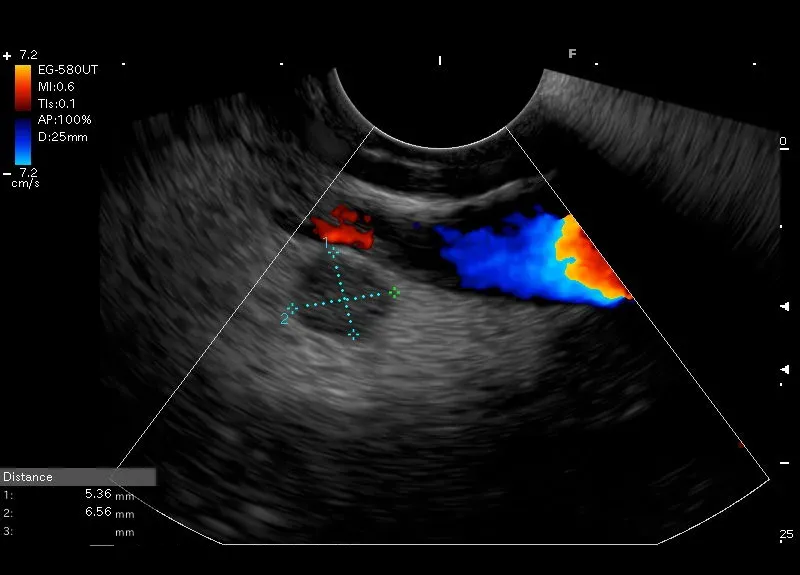

Hipoechogeniczna, regularna zmiana ogniskowa , bez przepływu w opcji Doppler, położona w wyrostku haczykowatym trzustki -obraz sugeruje NET